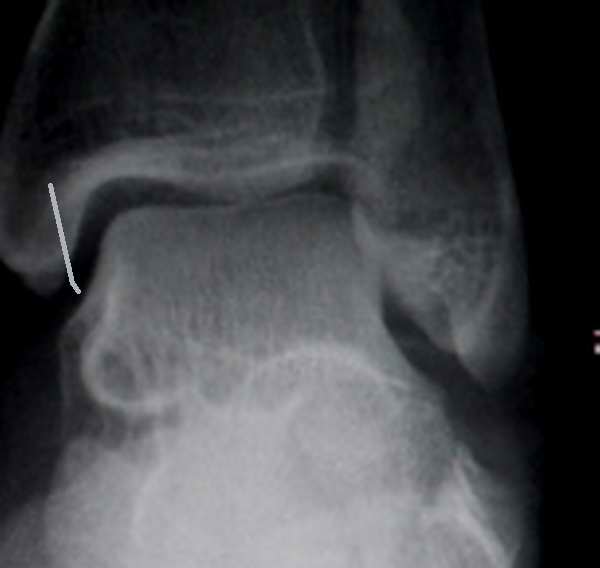

以下是引用黑白光影在2010-4-10 20:37:00的发言:[br]跟骨骨折。外踝也可能有骨折(外踝软组织很肿),距骨内侧有可能是楼主说的是重叠影也有可能是撕裂性骨折,只是在屏上翻拍片子不清楚。

以下是引用眼睛在2010-4-11 7:04:00的发言:[br]跟骨骨折比较明显,距骨改变同意重叠影一说。

以下是引用zhanggenliang在2010-4-10 21:26:00的发言:[br]跟骨骨折,此片不能诊断外踝骨折,可以说可疑,距骨内侧支持楼主重叠影一说。可以ct检查,也可以过几天血肿吸收后复查